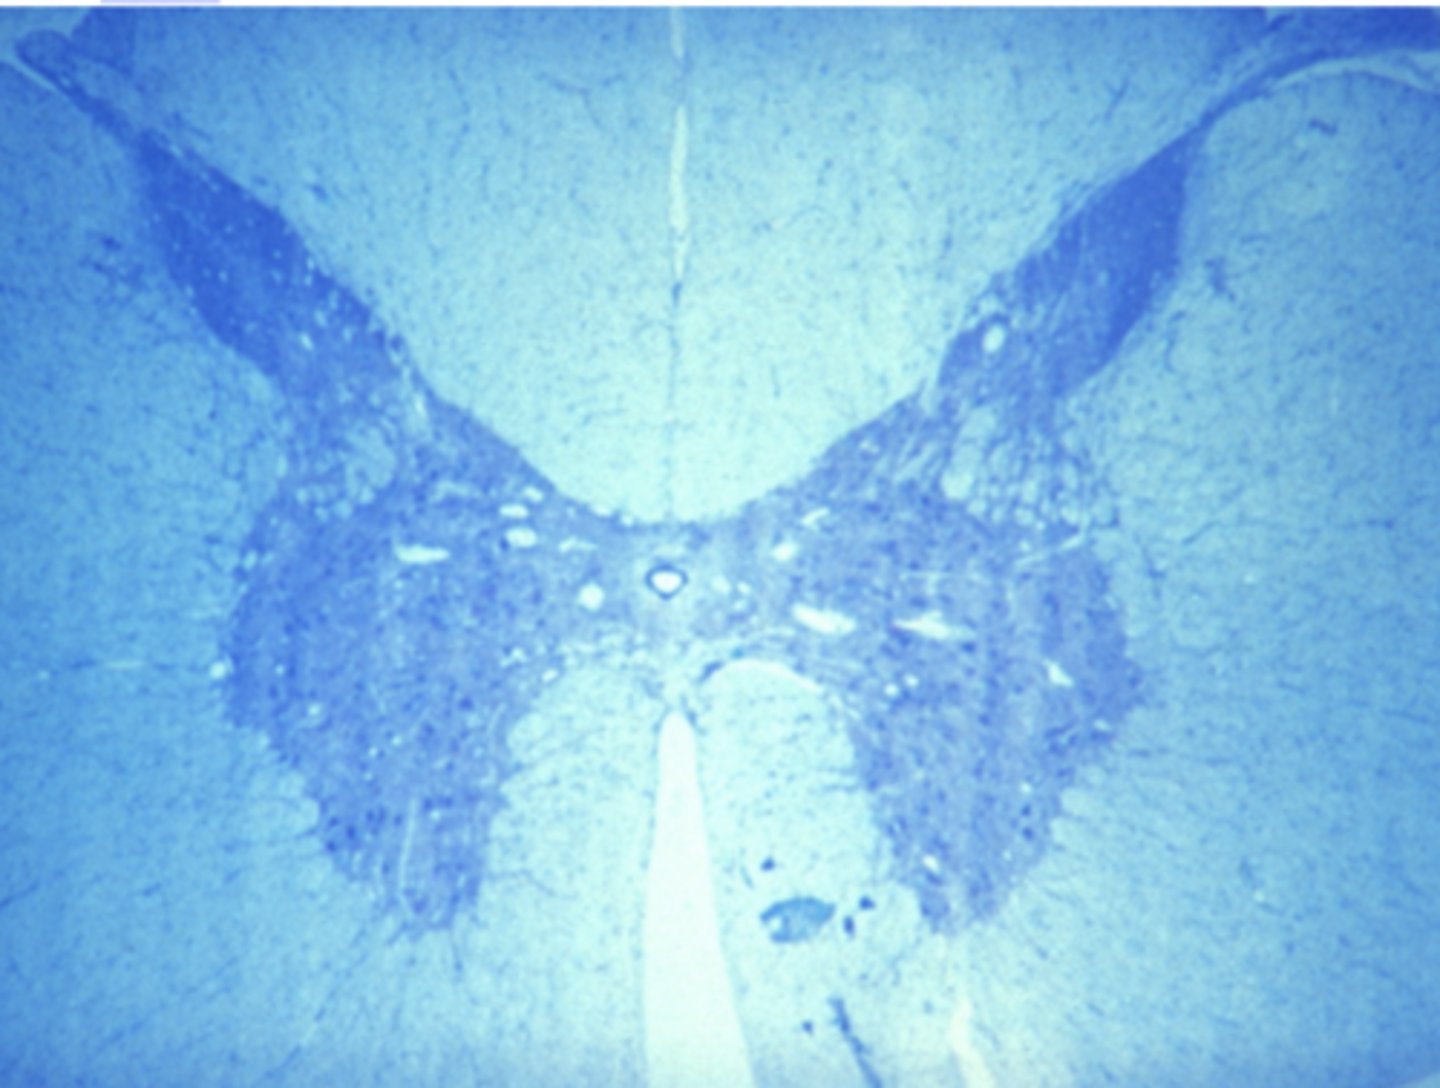

nervous tissue

Which of the four major tissue types is presented in the following image of the spinal cord:

Which of the four major tissue types is presented in the following image of the spinal cord:

Cells conduct electrochemical impulses

Which is a characteristic of the tissue type in the previous image (nervous tissue):

Cells have an apical and basolateral surface

Cells conduct electrochemical impulses

Cells are contractile

Cells produce an extracellular matrix